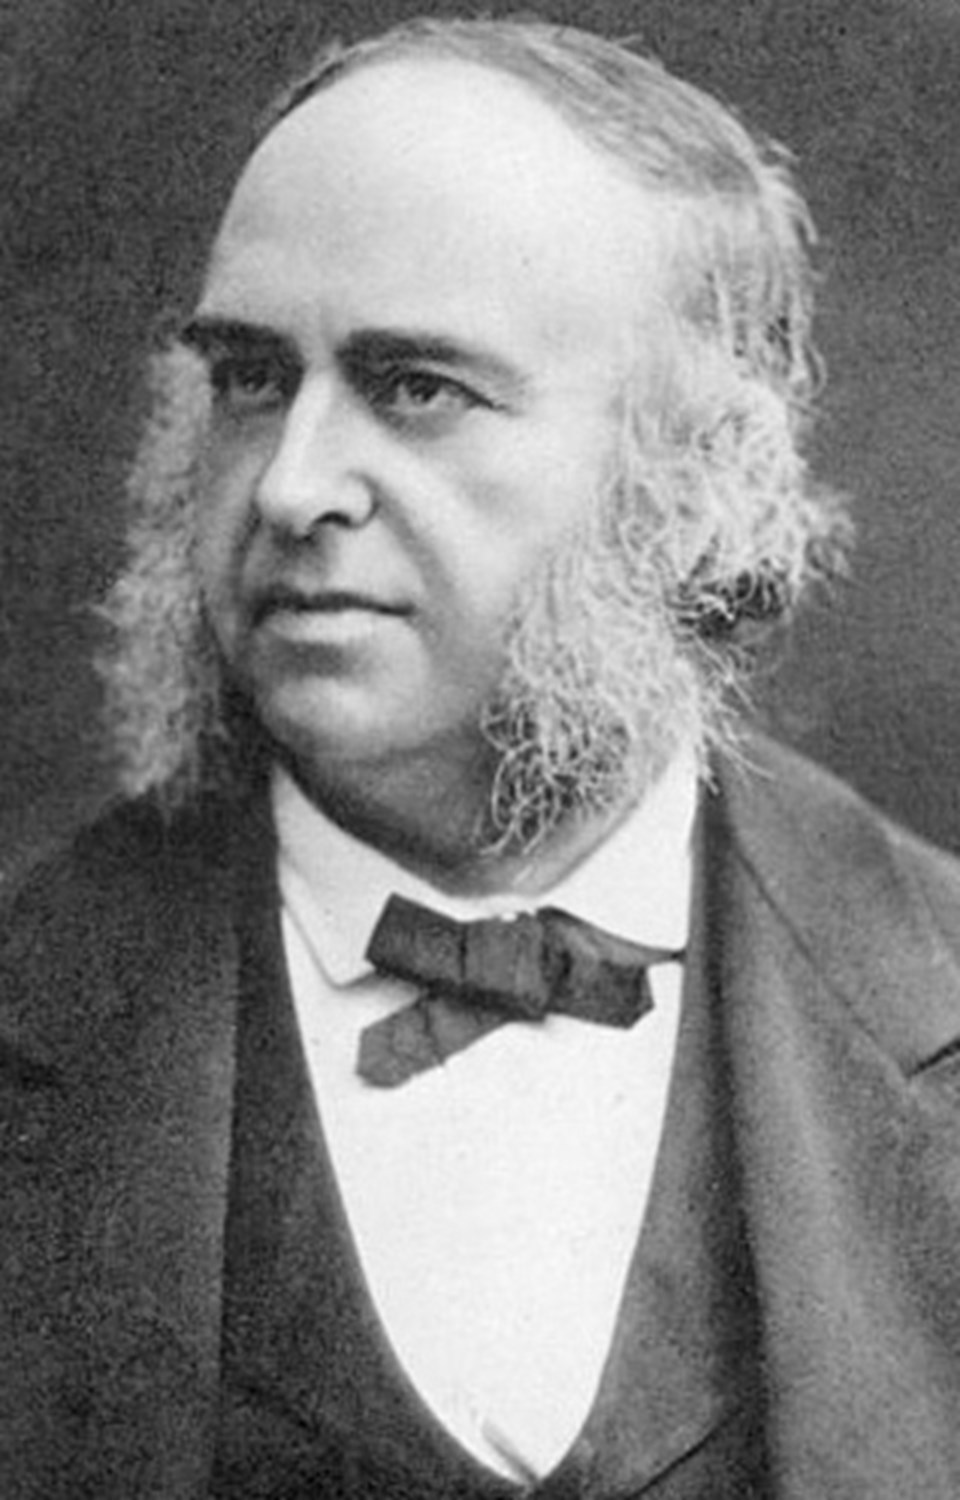

LiveScience’ın haberine göre, ölümünden kısa bir süre önce, Leborgne dönemin ünlü doktoru Paul Broca’ın odasına getirilmişti. Broca, hastası öldükten kısa bir süre sonra otopsi düzenledi.

Doktor Broca, Leborgne’nin beynini incelerken, gözlerin üstünde, arka kısımda doku bozulması tespit etti.

‘Tan’ lakabını alan hastasının beynini inceleyen Broca, tespit ettiği doku hasarının hastasının konuşma yetisini kaybetmesine neden olduğuna karar verdi. Anısını yaşatmak için, dil yeteneğinden sorumlu olan bölgeye, Broca’nın adı verildi.

Londra Üniversitesi’nde sinir bilimci olan Marjorie Lorch, LiveScience’a, “O dönemde bilim insanları beynin spesifik bölgelerinin farklı fonksiyonlardan sorumlu olup olmadığını tartışıyordu.. Tan, bu şüphelerin aşılmasını sağladı” dedi.

Polonya’nın Tıp Maria Curie-Sklodowska Üniversitesi’nde tıp tarihçisi olan Cezary Domanski ise “Tan, spesifik bir bölgenin konuşma yeteneğinden sorumlu olabileceğini gösteren tarihteki ilk vakaydı” ifadesini kullandı.